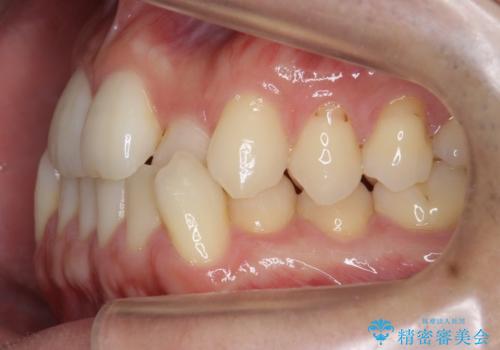

- 受け口を主訴に来院。

前歯の反対咬合でしたが、かみ合わせが、下顎が大きく前方にずれていました。

引っ込んでいる前歯の前方に下の犬歯が深く咬み込んでおり、また、奥歯のかみ合わせも受け口方向にずれ、骨格性の反対咬合も少々ありました。

上の前歯を前方に出すだけでは治療ができないため、ミニスクリューを用いて下の奥歯を後ろに送っています。

また、下の前歯を0.3mmずつIPRしています。